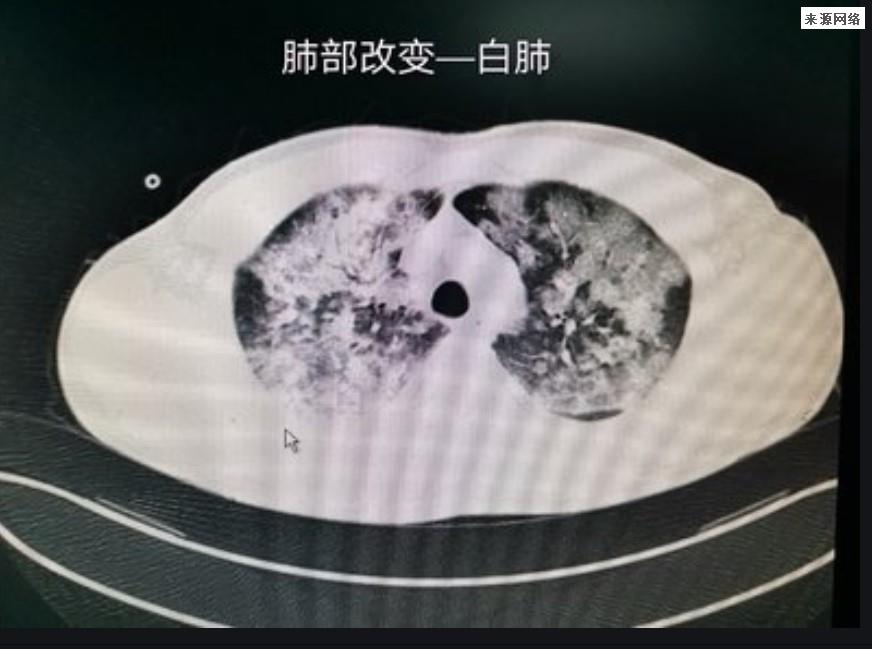

提前预警“白肺”有3个办法